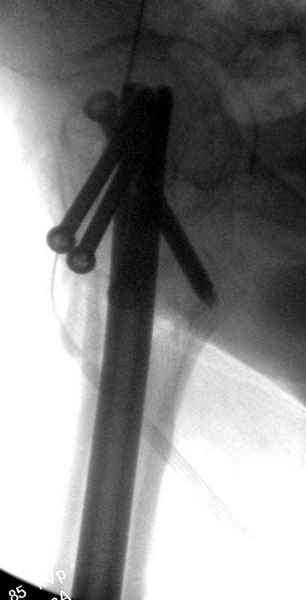

Профилактику дальнейшего раскола неполного перелома шейки провели тремя канюлированными шурупами.

На второй день после выписки упал дома. Снимки приложены. Коллеги рекомендуют удаление шурупа и вытяжение. Что делать?

Правильно, ситуация изменилась, как говорят у нас теперь "different animal", надо решать проблему подвертельного перелома. При наличии различных вариантов фиксаторов, включая Страйкер Гамма 3, мы выбрали DePuy Antegrade Trachanteric Nail из-за многовариантности проксимальной фиксации и двойного изгиба. Вводится через вертел под 8 градусным углом, и есть достаточный передний диафизарный изгиб, предупреждающий пенетрацию дистального переднего кортекса.